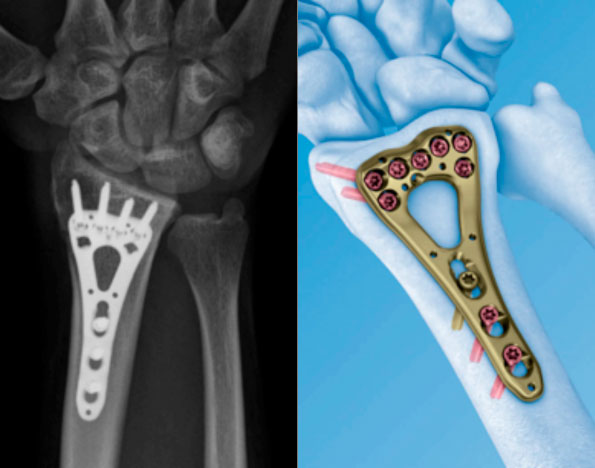

Beispiel eines handgelenksnahen Bruches der Elle (Firma Depuy Synthes) und Beispiel einer Speichenfraktur (Depuy Synthes)

Eines der gängigsten Op-Verfahren stellt die sogenannte volare (Zugang am Handgelenk von der Handinnenfläche betrachtet), winkelstabile Plattenosteosynthese dar. Hierbei handelt es sich um spezielle, anatomisch vorgeformte kleine Plattensysteme. Bei der dorsalen Osteosynthese erfolgt der Zugang von der Handrückenfläche aus. Mit Hilfe dieser modernen Implantate ist es möglich auch im osteoporotischen Knochen eine sichere, stabile Osteosynthese zu erzielen. Der grösste Vorteil gegenüber der konservativen Therapie ist, dass unmittelbar postoperativ damit begonnen werden kann das Handgelenk aktiv zu beüben. Abstützende Bewegungen oder das Tragen von Lasten sollte mindestens für die ersten 6 Wochen vermieden werden.

Winkelstabile Osteosynthese (Depuy Synthes)